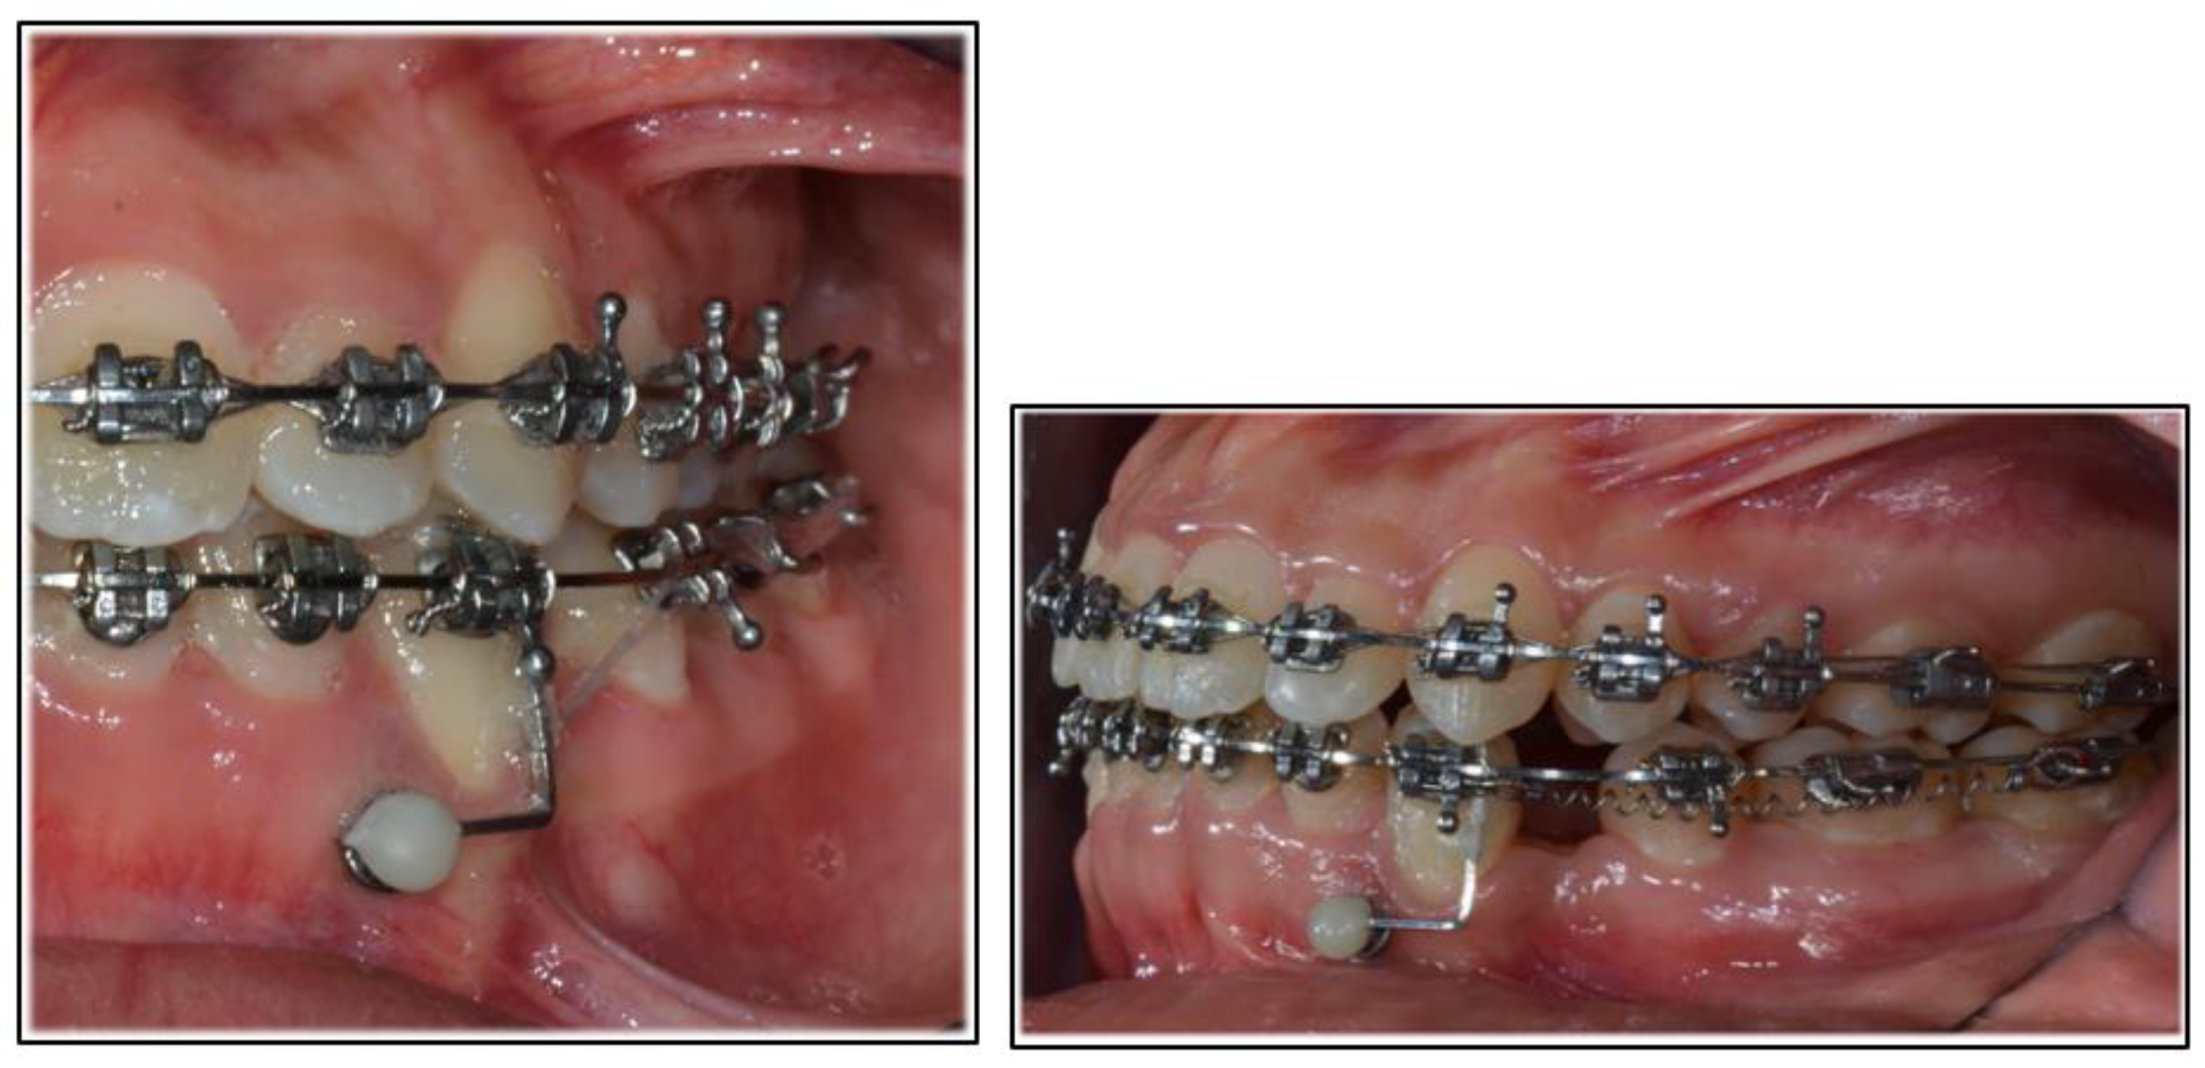

2. Case Report

2.2. Treatment Progress